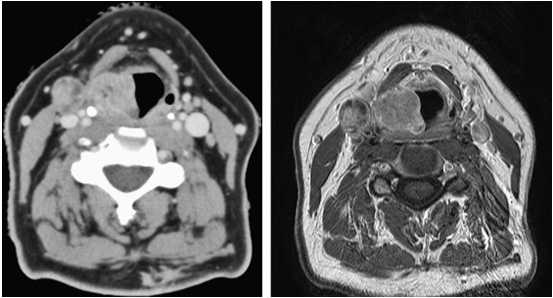

Сравнение КТ и МРТ мягких тканей шеи при раке правой голосовой складки. Один и тот же пациент. Слева КТ, справа МРТ.